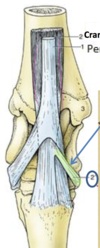

Which tendon is highlighted in green?

Cunean tendon